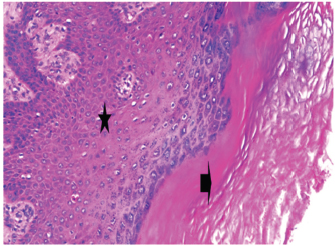

At 7 days post wounding; the inflammatory reaction was moderate and characterized by polymorphonuclear cells and macrophages infiltration with the presence of small scab covering the wound surface. Early evidence of epithelization was detected and represented by the proliferation of epidermal epithelium under the scab. There was marked thickening and hyperplastic proliferation of epidermal epithelium at the free wound edge (Fig. 6). The dermal tissue underlying the wound area showed few polymorphonuclear cells infiltration and more abundant mononuclear cells. Fibroplasia and angiogenesis were detected in the dermis and more extensive in deeper areas of the dermis which characterized by fibroblast and angioblast proliferation forming immature young granulation tissue (Fig. 7). At 14 days post wounding, the wound area was covered by a complete layer of epidermal epithelium indicating a good epithelization rate of the wound. Proliferation of cutaneous appendages was detected. The newly formed epithelium was thick and showed partial keratinization and epithelial differentiated stratum containing polyhedral keratinocyte with the appearance of keratohyalin granules in their cytoplasm (Fig. 8). The dermal tissue showed deposition of parallel well organized and interconnected collagen bundles that arranged parallel to epidermis associated with enhanced angiogenesis represented by well-developed blood capillaries (Fig. 9). At 21 days post wounding, remodeling of the formed epithelium with relatively small scar formation and mild restoration of skin appendages. Keratinized and differentiated stratum comprising the covering epithelium and the newly formed skin appendages from the basal epidermal epithelium were detected (Fig. 10). The dermal tissue revealed well-formed organized tissue consisted of parallel compact and interconnected bundles of collagen with scant angiogenesis (Fig. 11). At 28 days post wounding, well-formed scar tissue covering highly cellular organized tissue was detected (Fig. 12). The dermal tissue revealed well-arranged compact collagen bundles containing scarce blood vessels (Fig. 13).

Fig. 8. Skin of a goat from electroacupuncture group at 14 days post wounding showing enhanced reepithelization evidenced by differentiated polyhedral keratinocytes in the stratum spinosum and keratohyalin granules in the stratum granulosum (arrow) and keratinization (arrow head), (HE ×100).

Fig. 9. Skin of a goat from electroacupuncture group at 14 days post wounding showing well organized and interconnected collagen bundles that arranged parallel to each other and to epidermis (arrow head) associated with enhanced angiogenesis represented by well-developed blood capillaries (arrow), (HE ×200).